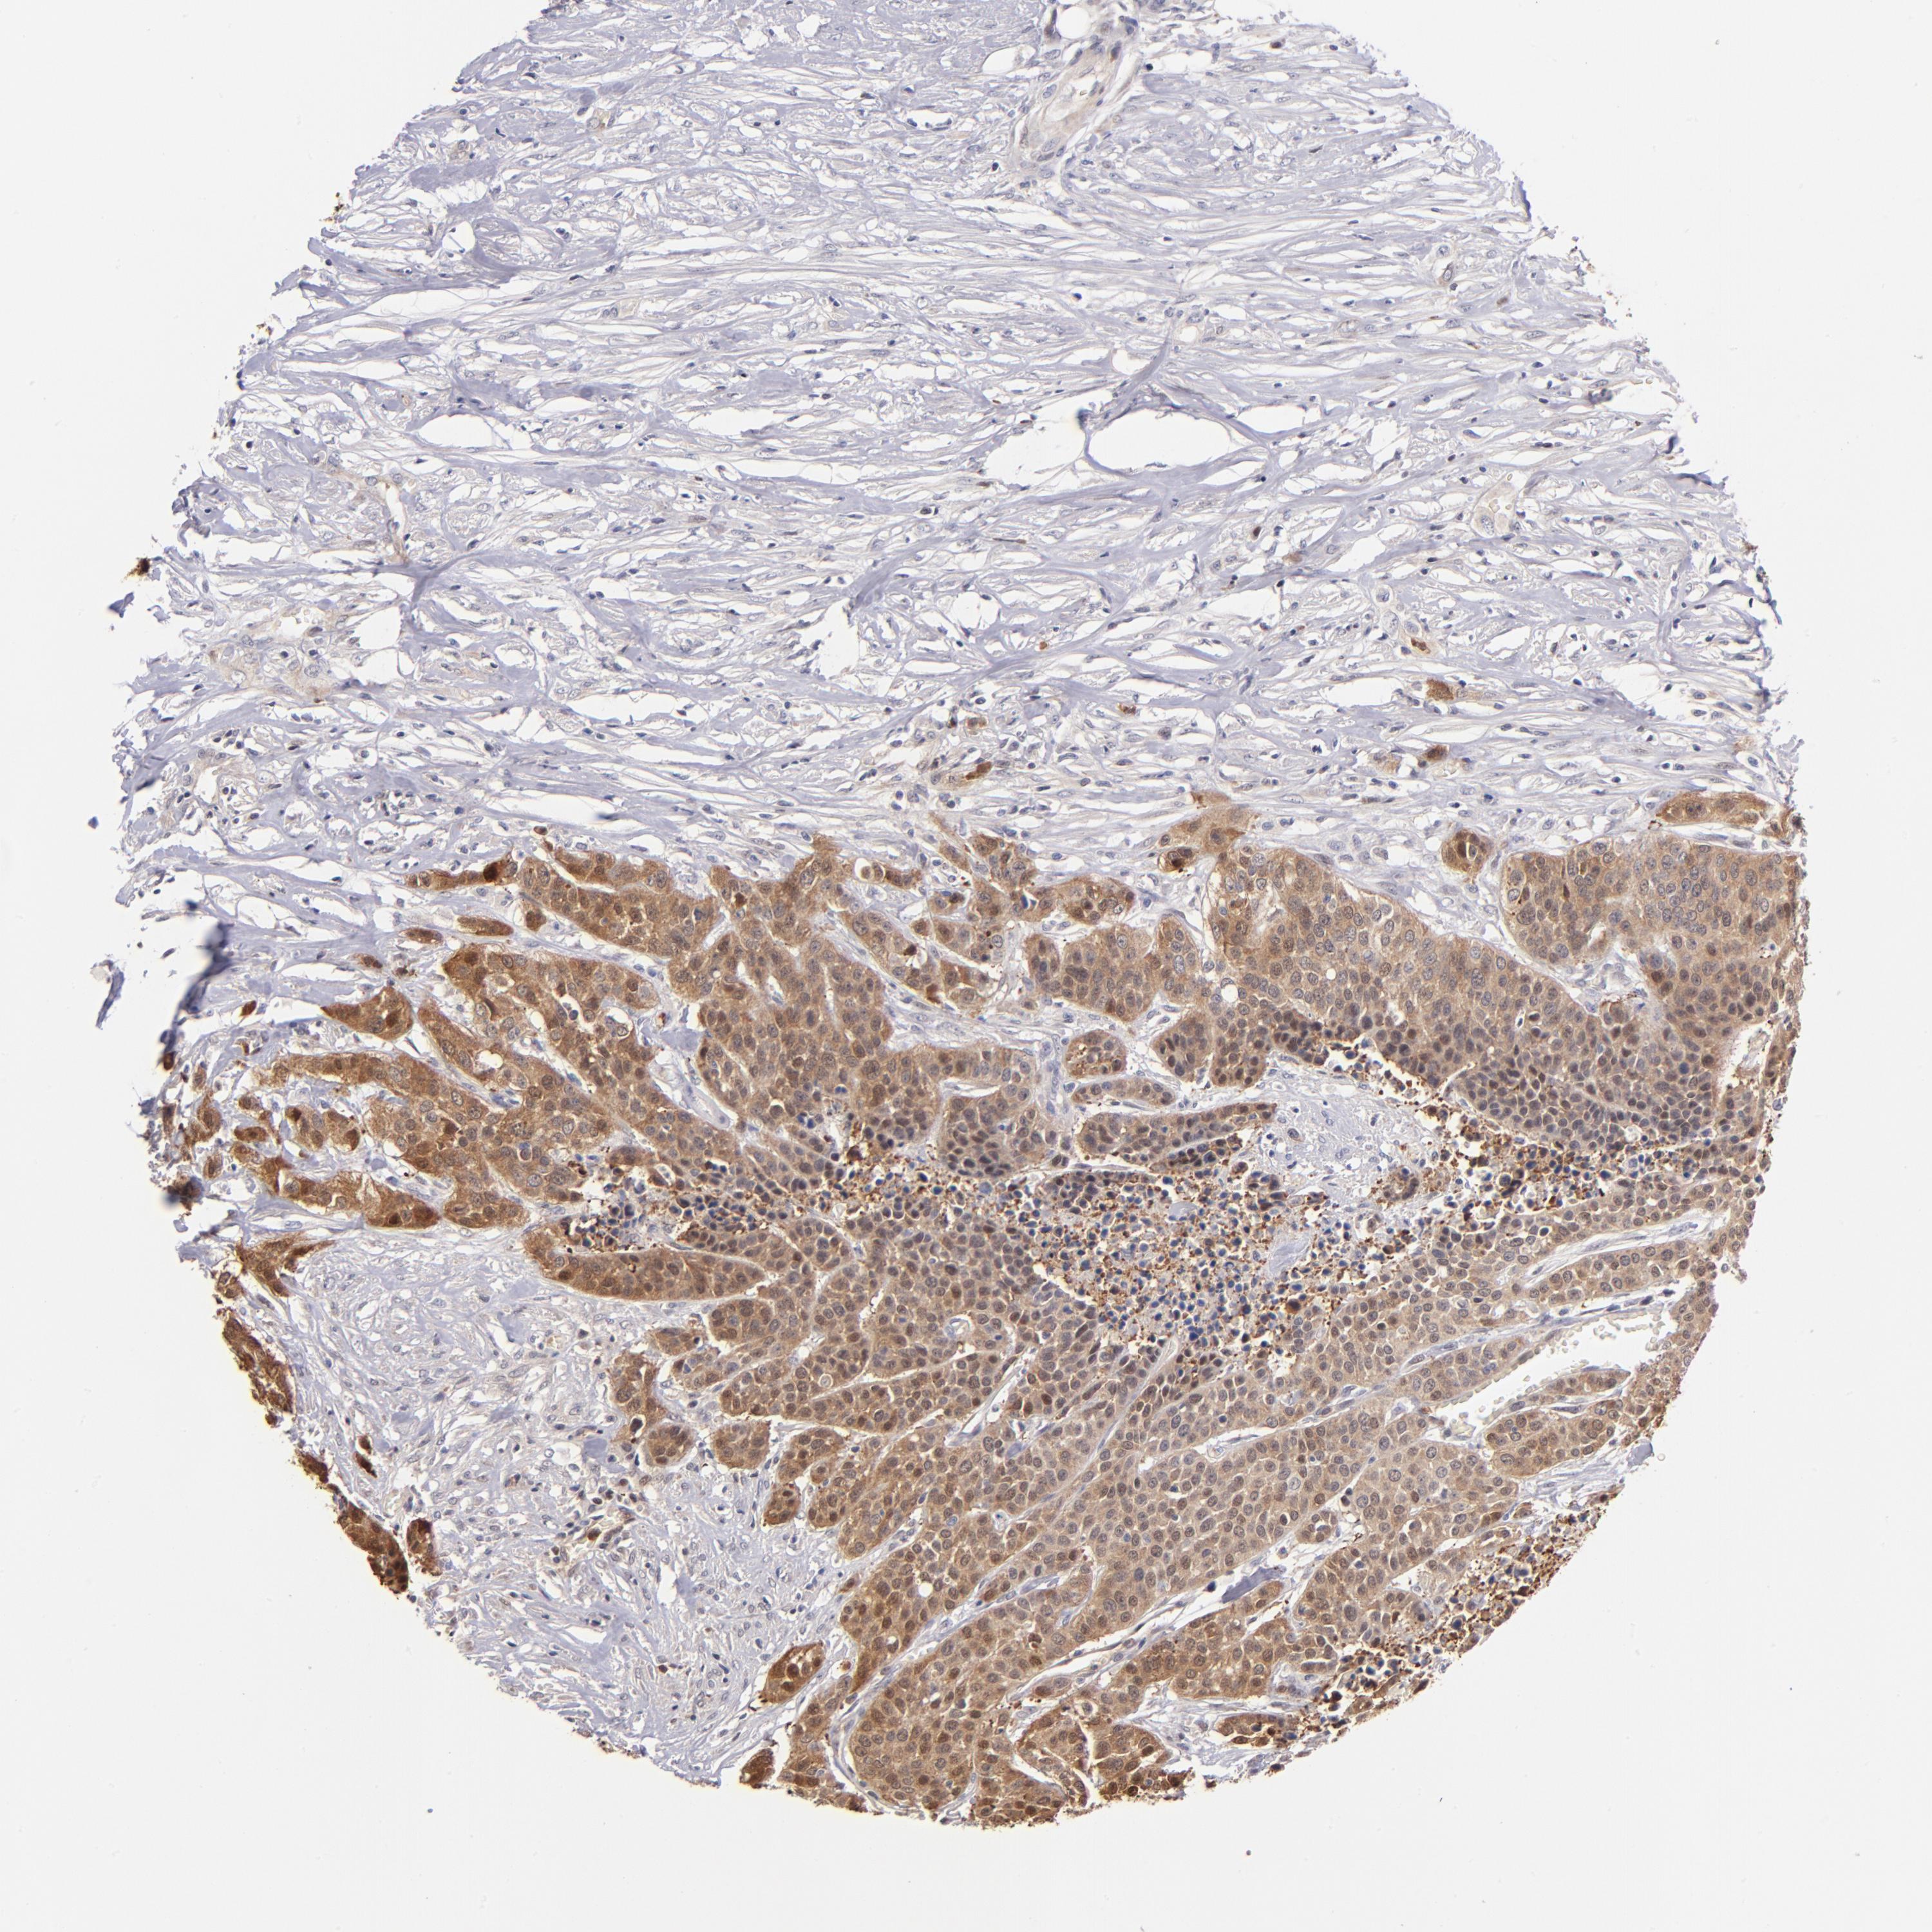

UROTHELIAL CANCER - Protein expressioni

A mouse-over function shows sample information and annotation data. Click on an image to view it in a full screen mode. Samples can be filtered based on level of antibody staining by selecting one or several of the following categories: high, medium, low and not detected. The assay and annotation is described here.

Note that samples used for immunohistochemistry by the Human Protein Atlas do not correspond to samples in the TCGA dataset.

Antibody stainingi

Antibody staining in the annotated cell types in the current human tissue is reported as not detected, low, medium, or high, based on conventional immunohistochemistry profiling in selected tissues. This score is based on the combination of the staining intensity and fraction of stained cells.

Each image is clickable and will lead to virtual microscopy that enables deeper exploration of all samples and also displays staining intensity scores, fraction scores and subcellular localization as well as patient and tissue information for each sample.

Antibody HPA007925

Antibody HPA011212

Antibody CAB003759

Antibody CAB080290

Urothelial carcinoma, Low grade

Urothelial carcinoma, High grade